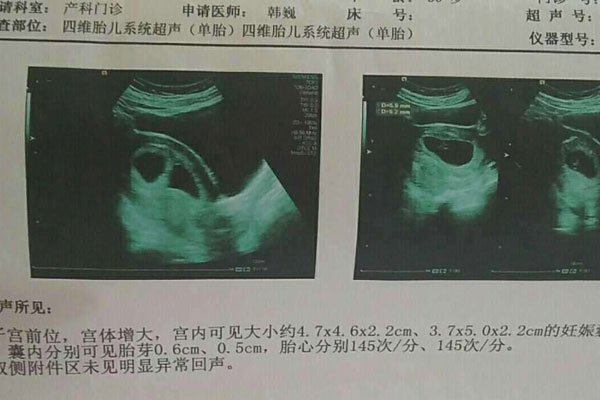

医生说怀男孩的特点 三个特征有一个就是重男轻女(2)

医生说怀男孩的特点 三个特征有一个就是重男轻女

怀男孩特点